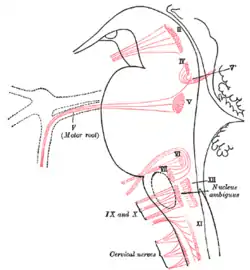

Nuclei of origin of cranial motor nerves schematically represented; lateral view.

Nuclei of origin of cranial motor nerves schematically represented; lateral view. Primary terminal nuclei of the afferent (sensory) cranial nerves schematically represented; lateral view.